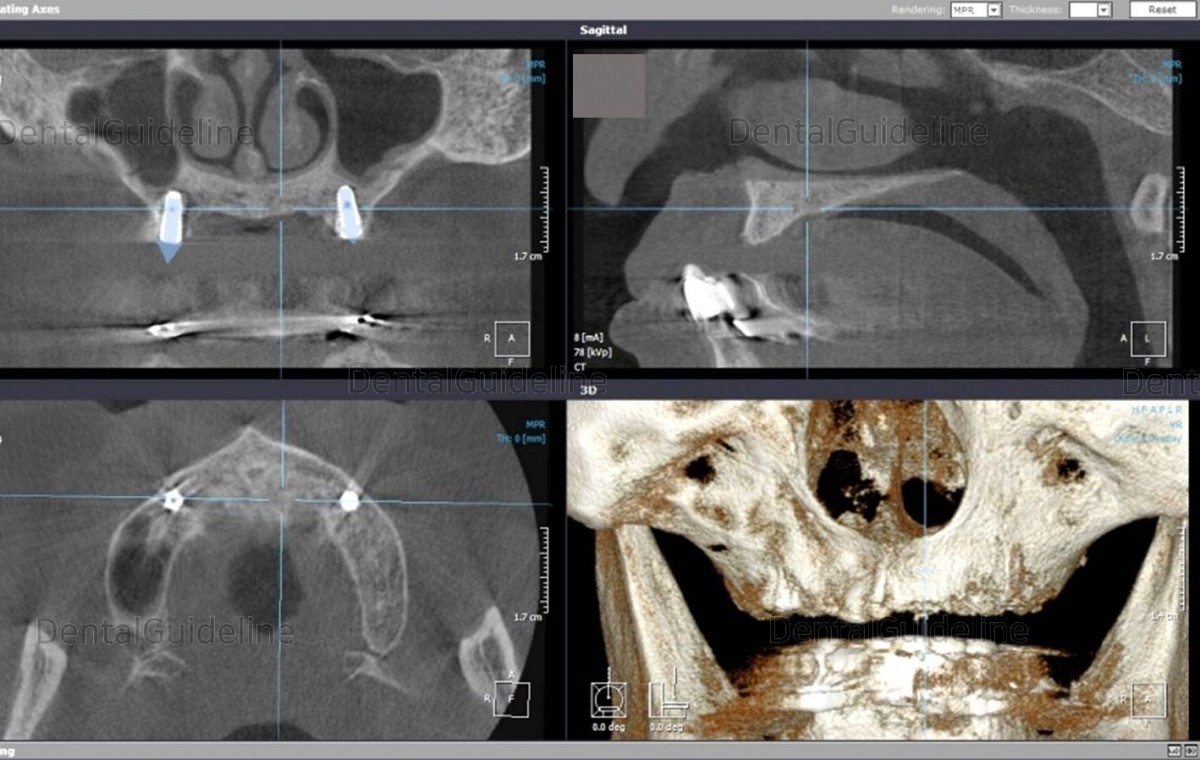

After filling the hole with a radiopaque material (Caviton®), take a radiograph to determine the implant placement location.